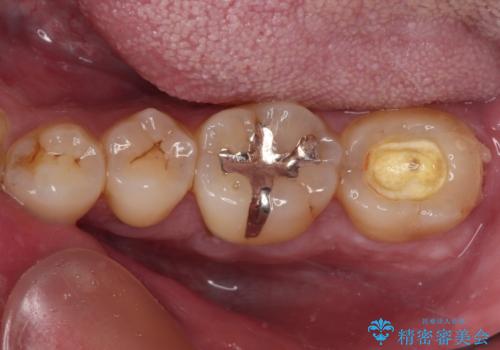

- 職場近くで通っていた医院の先生が体調不良で診療できなくなったとのことで、転院されてきた患者様です。

既に根管治療を終えている状態での来院で、クラウンを装着を希望されていらっしゃいました。

レントゲン写真より根管治療のやり直しをお勧めしたところ、ラバーダム使用下で処置を行うことを希望されたため、根管治療を行った後にオールセラミッククラウンにて補綴治療を行うこととしました。